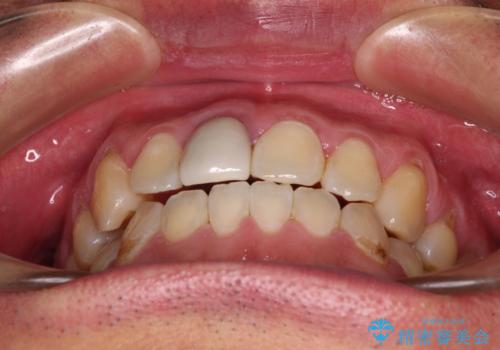

前歯のデコボコとクロスバイトをインビザライン矯正で改善

- 前歯のデコボコと上下のクロスバイトを気にして来院された患者様です。

インビザラインを用い、IPR(歯と歯の間を削る)と歯列全体を拡大させることで、歯並びを整えていくこととしました。

上の前歯が下の前歯を乗り越える際、奥歯がほとんど咬めない時期があり、乗り越えた後も、インビザライン特有の奥歯の咬みにくさが続きました。

咬み合わせ改善のために治療期間を要しましたが、最終的に奥歯はしっかりと咬めるようになりました